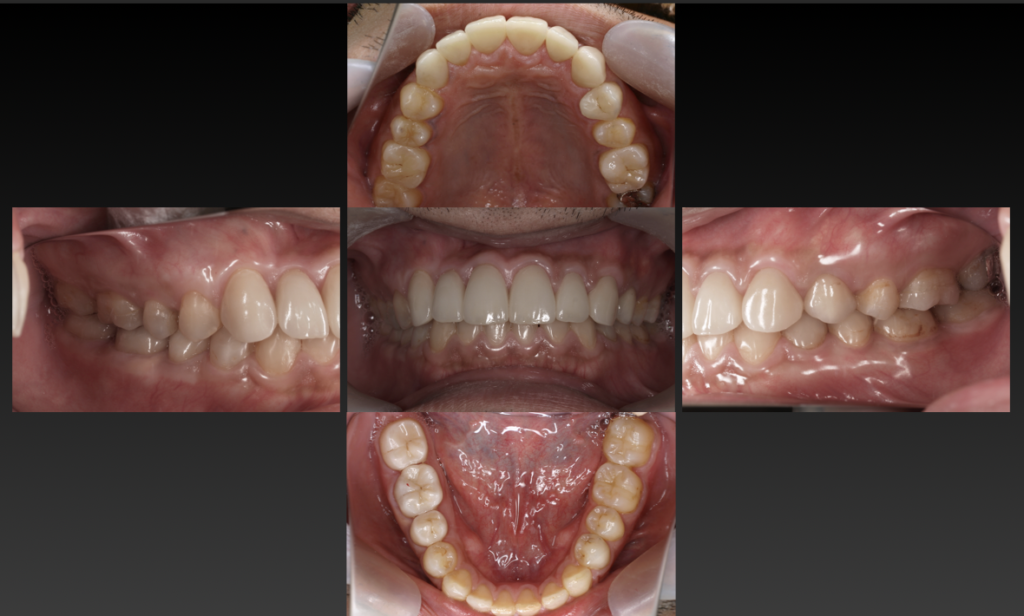

| 治療方法 | 食生活、生活習慣の乱れからの虫歯による咬合崩壊症例 全体的な歯周治療、プラスチックの治療用の歯による咬合治療後、コンポジットレジンとセラミックによる咬合再構成。 咬合治療とはお口の中をひとつの単位と捉え、咬み合わせや審美性、顎関節などをトータルに治療していきます。口腔内の崩壊をきたしてしまった患者さんに対して、悪くなってしまった原因を追求し、次は悪くならないように、機能面、清掃性、審美性のトータル治療が「全顎治療(フルマウスリコンストラクション)」です。虫歯や歯周病になってしまった歯を1本だけ治すのではなく、お口全体を考慮して長期的な視野に立った健康維持を行うために治療計画を立てていきます。 劇的なスマイルの改善、食生活も見直していただき肌つやも良くなりお顔の印象が大きく変化しました。公私ともに周囲の評価も上がったと非常に喜んでいただきました。 虫歯だから詰めて終わるのではなく、なぜ虫歯になったのかを追求し歯科治療にあたりました。 |

| 通院期間・通院回数 | 約1年 |

| 費用 | ・咬合治療費 200,000 ・セラミック修復 臼歯部 90,000 × 7本 ・前歯部 120,000 × 6本 ・他 健康保険治療(歯周治療、根管治療、コンポジットレジン修復14箇所) |